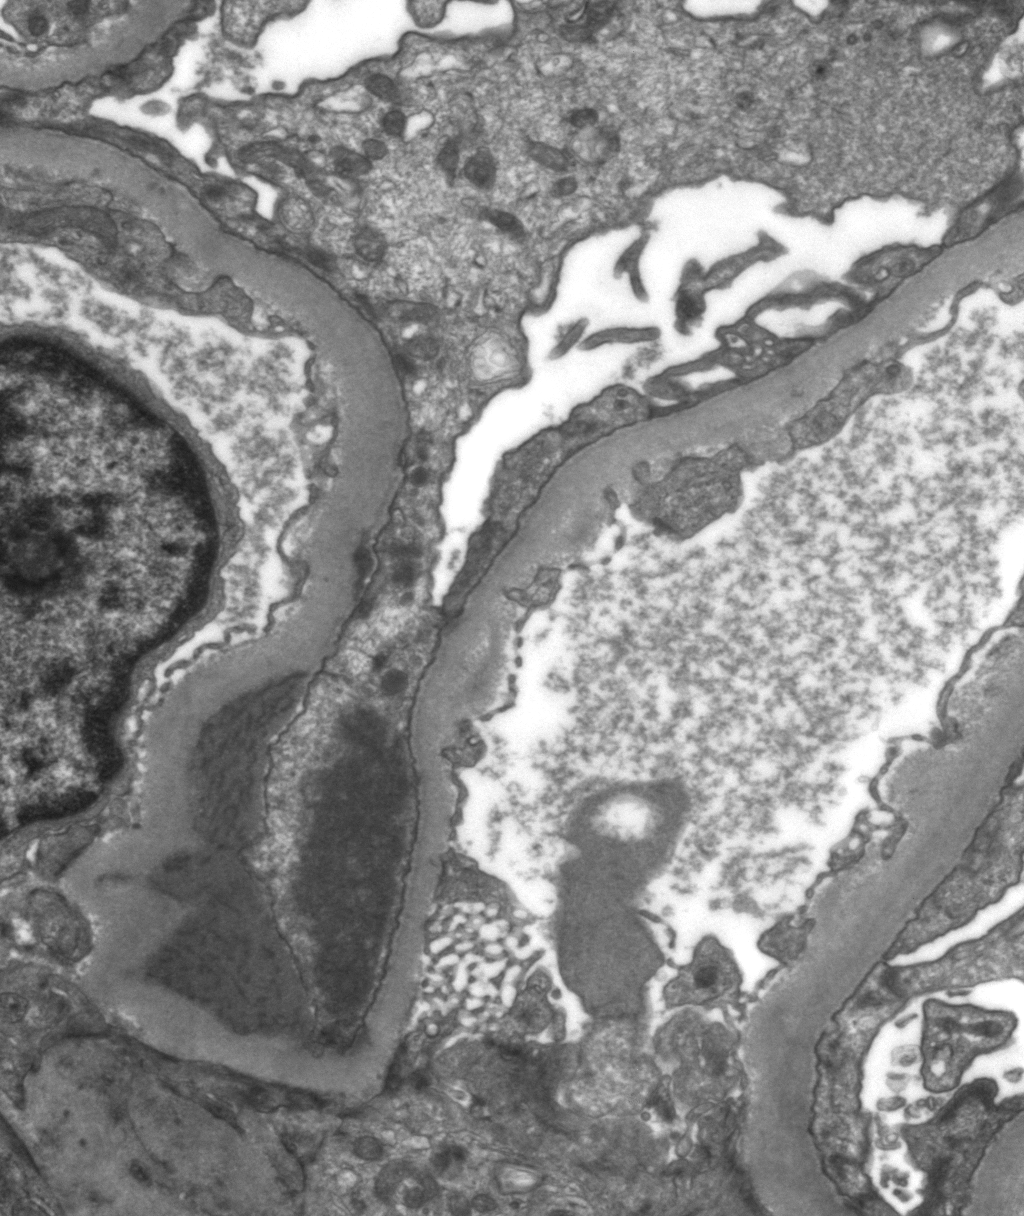

- 0.3cm - 0.5cm of cortex with glomeruli for glutaraldehyde, EM